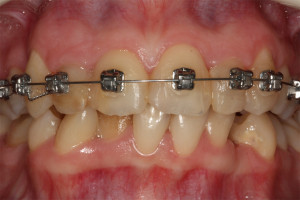

Młoda pacjentka zgłosiła się do naszego gabinetu celem wykonania kompleksowego leczenia zachowawczo-ortodontycznego. Oprócz problemów natury ortodontycznej stwierdzono złą higienę jamy ustnej oraz liczne potrzeby leczenia zachowawczo-endodontycznego. Po wnikliwej analizie telerentgenowskiej oraz analizie modeli zadecydowano o ekstrakcji 2 zębów w łuku dolnym (kła po stronie lewej oraz pierwszego przedtrzonowca po stronie prawej). Plan leczenia obejmował ponadto zamknięcie łuku po brakujących zębach w łuku górnym. Leczenie aktywne trwało 2 lata i 8 miesięcy. W czasie jego trwania pacjentka była regularnie poddawana zabiegom higieny profesjonalnej celem eliminacji zapaleń przyzębia brzeżnego. Po leczeniu aktywnym zastosowano leczenie retencyjne w postaci retainera stałego w żuchwie oraz szyny retencyjnej w łuku górnym.